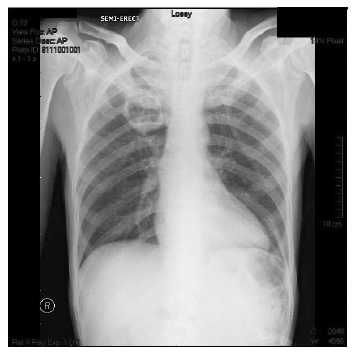

Figure 1. A posteroanterior chest radiograph demonstrating pulmonary infiltration and a cavitary lesion in the superior lobe of the right lung.

Signs of acute rejection were observed during the third posttransplant month in a 47-year-old man who, at our institution in September 2007, received an orthotopic heart transplant as treatment for dilated cardiomyopathy. This patient’s laboratory test results were seronegative for CMV during the pretransplant period, but the CMV serologic status of the donor was unknown. The patient was treated with cyclosporine (15 mg/kg) and mycophenolate mofetil (2 × 1.5 g) and received prophylaxis against CMV (intravenously administered ganciclovir (2 × 5 mg/kg induction treatment for 2 weeks and 2 × 2.5 mg/kg maintenance treatment) for 1 month and oral valganciclovir (2 × 450 mg) for 2 months as a standard posttransplant regimen. To treat rejection, he received pulsed steroids, a few days after which dyspnea, cough, purulent sputum, and a fever of 38.5ºC developed. The patient was diagnosed as having pneumonia, and treatment with ceftriaxone (1 × 2 g intravenously administered) was initiated. That initial treatment was replaced with piperacillin-tazobactam (4 × 4.5 g intravenously administered) anti¬biotic therapy because tachycardia (102 beats/min), tachypnea (22 breaths/min), and fever persisted, and the patient’s orientation and ability to cooperate deteriorated. The results of biochemical testing revealed the following values: white blood cell count, 5.1 × 109/L; hemoglobin value, 8.3 mmol/L; platelet count, 14 × 109/L; aspartate transaminase, 74 U/L; alanine transaminase, 46 U/L; alkaline phosphatase, 2972 U/L; γ-glutamyltransferase, 803 U/L; L-lactate dehydrogenase, 2177 U/L; total bilirubin, 61.1 µmol/L; and direct bilirubin, 44.3 µmol/L. Treatment with ganciclovir 2 × 5 mg/kg was added to the regimen because the patient exhibited bicytopenia; elevated liver enzymes; cerebral symptoms; and the following values: CMV pp65 antigen, > 8 antigen-positive cells/2 × 105 peripheral blood leucocytes; and CMV real-time polymerase chain reaction results, 31 245 copies/mL, all of which indicated CMV infection. Bronchoscopy was not performed because of the patient’s severe thrombocytopenia, and the histopathologic findings did not confirm CMV pneumonia. Extended spectrum beta-lactamase–producing Klebsiella pneumoniae was grown in the sputum culture, and piperacillin-tazobactam was replaced with carbapenem Meropenem (3 × 1 g intravenously administered). Despite treatment with ganciclovir and the meropenem, the patient required increasing support with oxygen and exhibited progressive dyspnea. A posteroanterior radiograph of the chest revealed pulmonary infiltration and a cavitary lesion in the superior lobe of the right lung (Figure 1). A thoracic computed tomographic scan showed bilateral nodular lesions with a halo sign, consolidated areas, and a cavitation (23 × 19 mm) in the superior lobe of the right lung (Figure 2). Coinfection with Aspergillus was suggested by the thoracic computed tomographic findings, and a galactomannan antigen index of 2.3 supported that diagnosis. Blood samples for serum galactomannan antigen levels were obtained 6 hours after the last administration (and just before the next administration) of the piperacillin-tazobactam infusion to prevent possible false-positive results. The patient was diagnosed as having probable invasive pulmonary aspergillosis and received parenteral voriconazole (a 2 × 6 mg/kg loading dose followed by a 2 × 4 mg/kg maintenance dose). His dyspnea, fever, and biochemical parameters were within normal limits at follow-up. Treatment with the meropenem was discontinued after 2 weeks and ganciclovir therapy was terminated after 4 weeks as the test results for CMV pp65 antigen and the CMV real-time polymerase chain reaction became negative. At the follow-up examination, the patient’s galactomannan levels had also decreased (Figure 3), and a control thoracic computed tomographic scan revealed the decreased dimensions of the nodules and cavity, the regression of parenchymal consolidation, and the resolution of the air-crescent sign in the cavitation (Figure 4). The radiologic findings are shown in Figure 2. The patient’s antifungal treatment was changed to oral voriconazole (2 × 200 mg), which was continued until all abnormal radiologic findings had resolved.